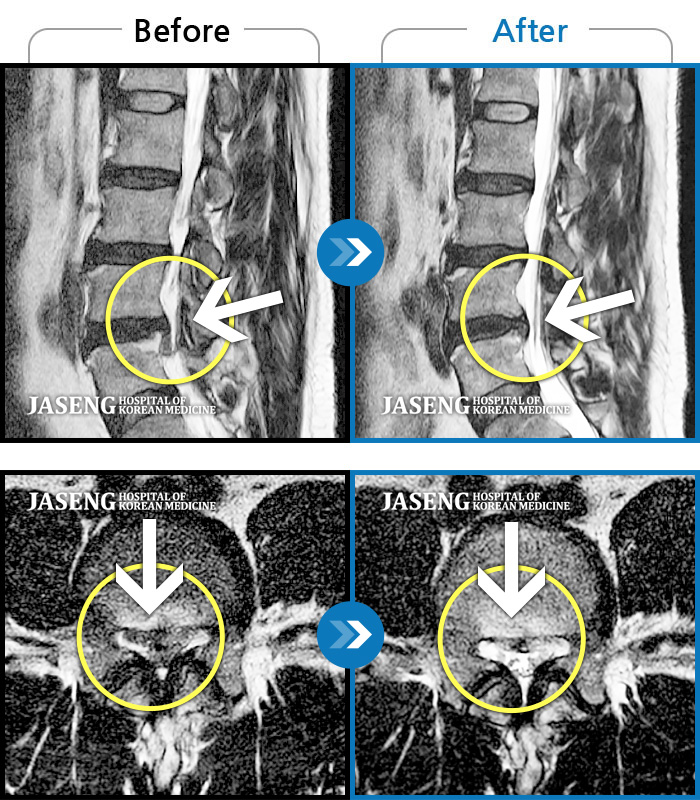

허리디스크

천안 · 김세정 원장

요추 디스크 파열로 극심한 통증을 동반하여 내원하였습니다

촬영시기

2021.12.18 ~ 2024.01.23